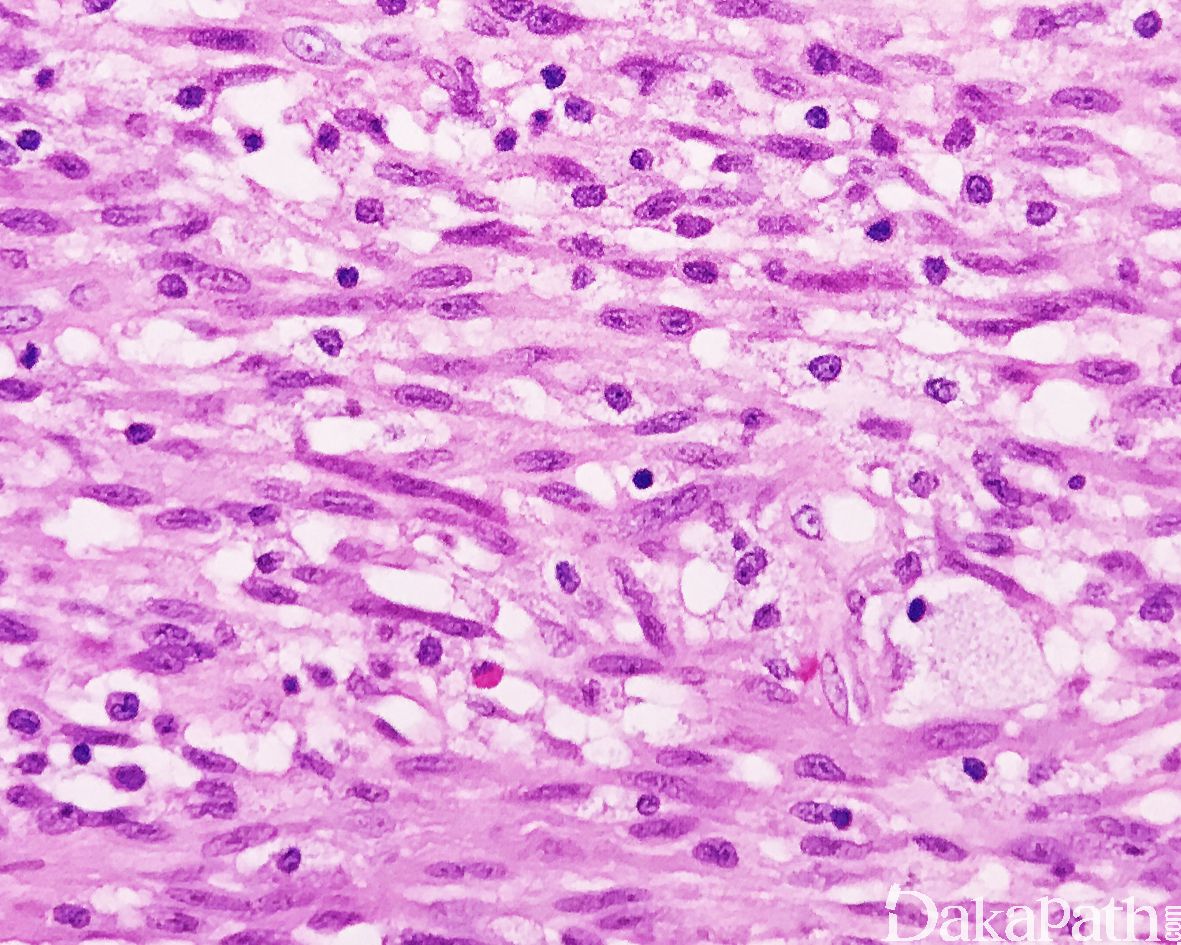

细胞质强嗜酸性,原纤维状,核呈长卵圆形,两端稍钝,多数病例可见散在的横纹肌母细胞;

瘤细胞的异型性不明显,可见少数核分裂像;